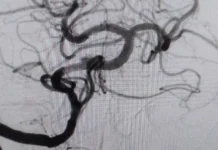

Благодаря высочайшему профессионализму медицинской бригады были приняты молниеносные решения. Специалисты виртуозно провели деликатное удаление тромба, после чего последовала филигранная операция по замене митрального клапана. Упорная борьба за жизнь пациентки увенчалась триумфальным успехом — спустя два с половиной месяца реабилитации женщина благополучно вернулась в родные стены.